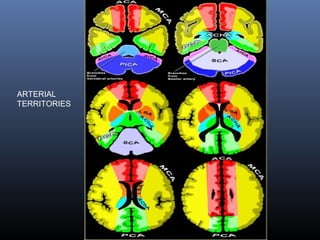

Blood supply of brain

Lateral view

Blood supply-Medial view

ARTERIAL

TERRITORIES